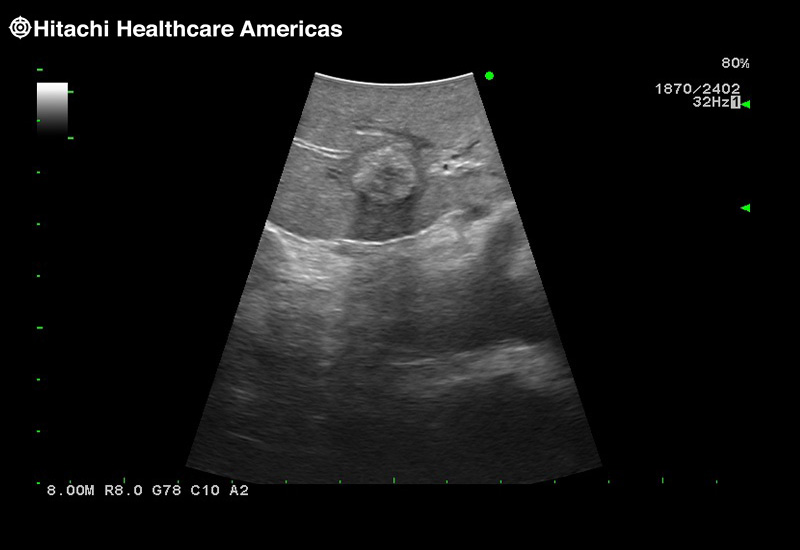

Our smallest footprint allows for enhanced contact in tight spaces

Our newest probe, the L51K allows the surgeon access to difficult-to-reach areas that no other probe on the market can go. The unique design and proximal location of the attaching mechanism provides full wrist articulation and easier grasp and release.

Imaging Clearly Defined

State-of-the-art digital architecture and advanced imaging features to redefine the capabilities of surgical ultrasound.